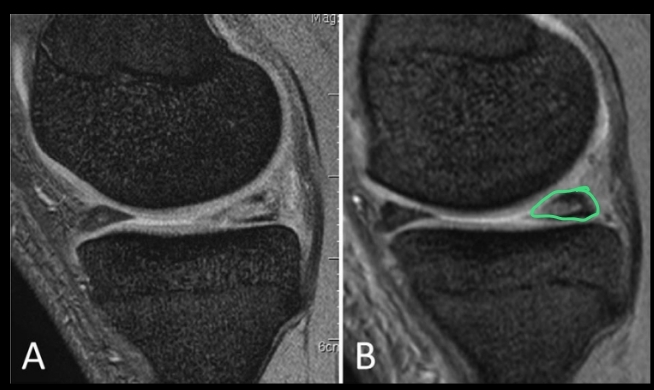

Cuál es el mejor estudio para ver un desgarro meniscal y qué permite ver?

RM

- Permite ver y caracterizar desgarros en múltiples planos